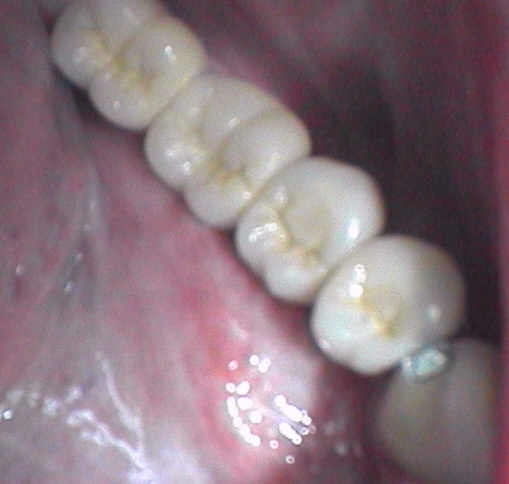

Die Anbindung der kurzen Implantate an 33 über ein Stressgeschiebe macht in mehrerer Hinsicht auf lange Sicht Sinn. Die Implantate sind kurz und schwach. Bei Überlastung ist es daher wünschenswert, dass sich die Brücke besser von den kurzen Aufbauten der Implantate löst als dass sich die Implantate selbst lockern.

Galerie: